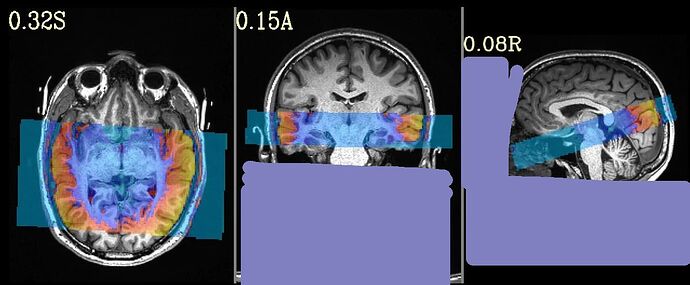

This is the beginning of output. When checking the volumes in original space, the images when applying obliquity look almost correct. That's what I acquired.